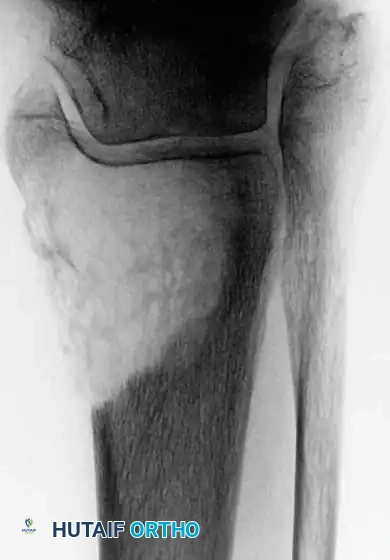

Fig. 22-19: (A) Anteroposterior view of the left hip of a 50-year-old woman with a history of breast cancer, disease-free for 2 years. A lytic lesion is seen in the femoral neck. Although the most likely diagnosis is metastatic carcinoma, a biopsy must be performed. This lesion proved to be a malignant fibrous histiocytoma (primary sarcoma). (B) Anteroposterior view after wide resection and endoprosthetic reconstruction. Prophylactic fixation of this presumed metastasis would have severely compromised her oncologic outcome.